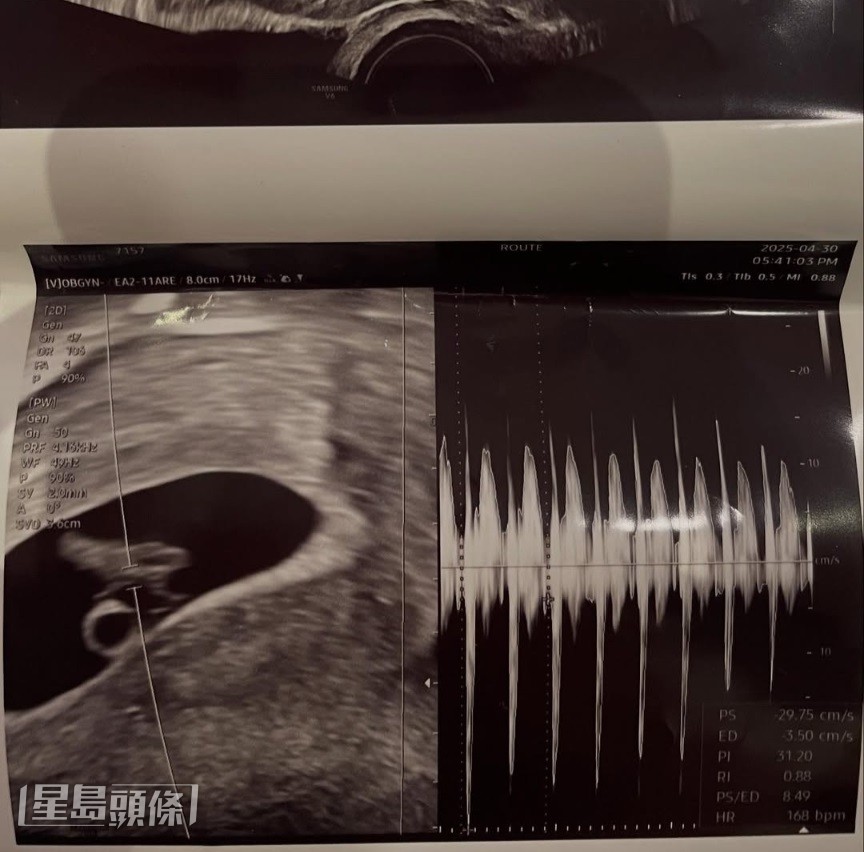

徐敏在日前在IG发文说:“恭喜你当爸爸了”,并附上一张胎儿的超声波照片,宣布怀孕消息。她更大晒一系列与男友的亲密合照,清楚展示对方样貌,甚至公开男友名字为郑某某,估计此人正是其腹中BB的“经手人”。及后在网民纷纷恭喜她及猜测其男友年龄时,徐敏在甚至公开男友是1997年出生,并在世宗大学就读。她接着继续公开二人一系列合照,当中更有男友靠在其胸前睡觉的亲密“床照”。最炸裂是徐敏在又公开了她与郑姓男友的短讯,徐敏在多次恳求对方联系:“联络一下吧”、“一直逃避想点?这么不负责任地让我怀孕后就抛下我,怎么办?”郑男则回应:“姐姐,我也因为这个突然的情况没办法立刻回覆,我现在好头痛,明天会联络妳,我们再好好谈谈。”而在公开BB超声波照的贴文中,徐敏在甚至标记了郑男的社交账号,对方吓得删除了该账号。看来是小男友“搞出人命”后却不想负责玩失联,故此徐敏在索性公开事件,施压逼对方联络她。

▲徐敏在于IG大晒胎儿超声波照,宣布怀孕。